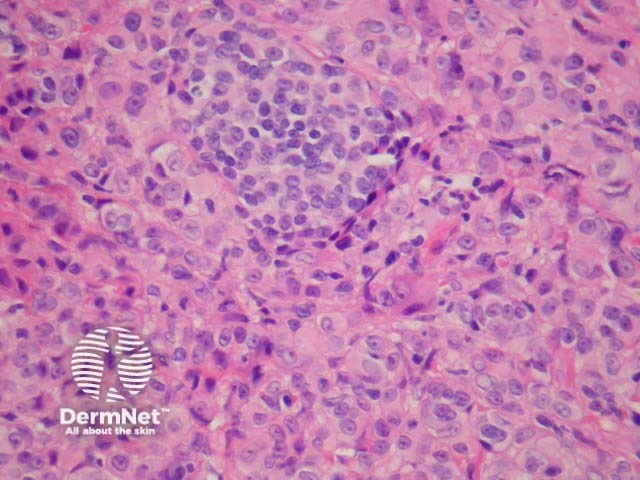

Rarely, melanoma which has metastasised to the dermis may closely mimic a blue naevus (blue naevus-like melanoma, figures 3,4). This can cause considerable diagnostic difficulty and be impossible to correctly recognise without clinical information.

Figure 3

Figure 4